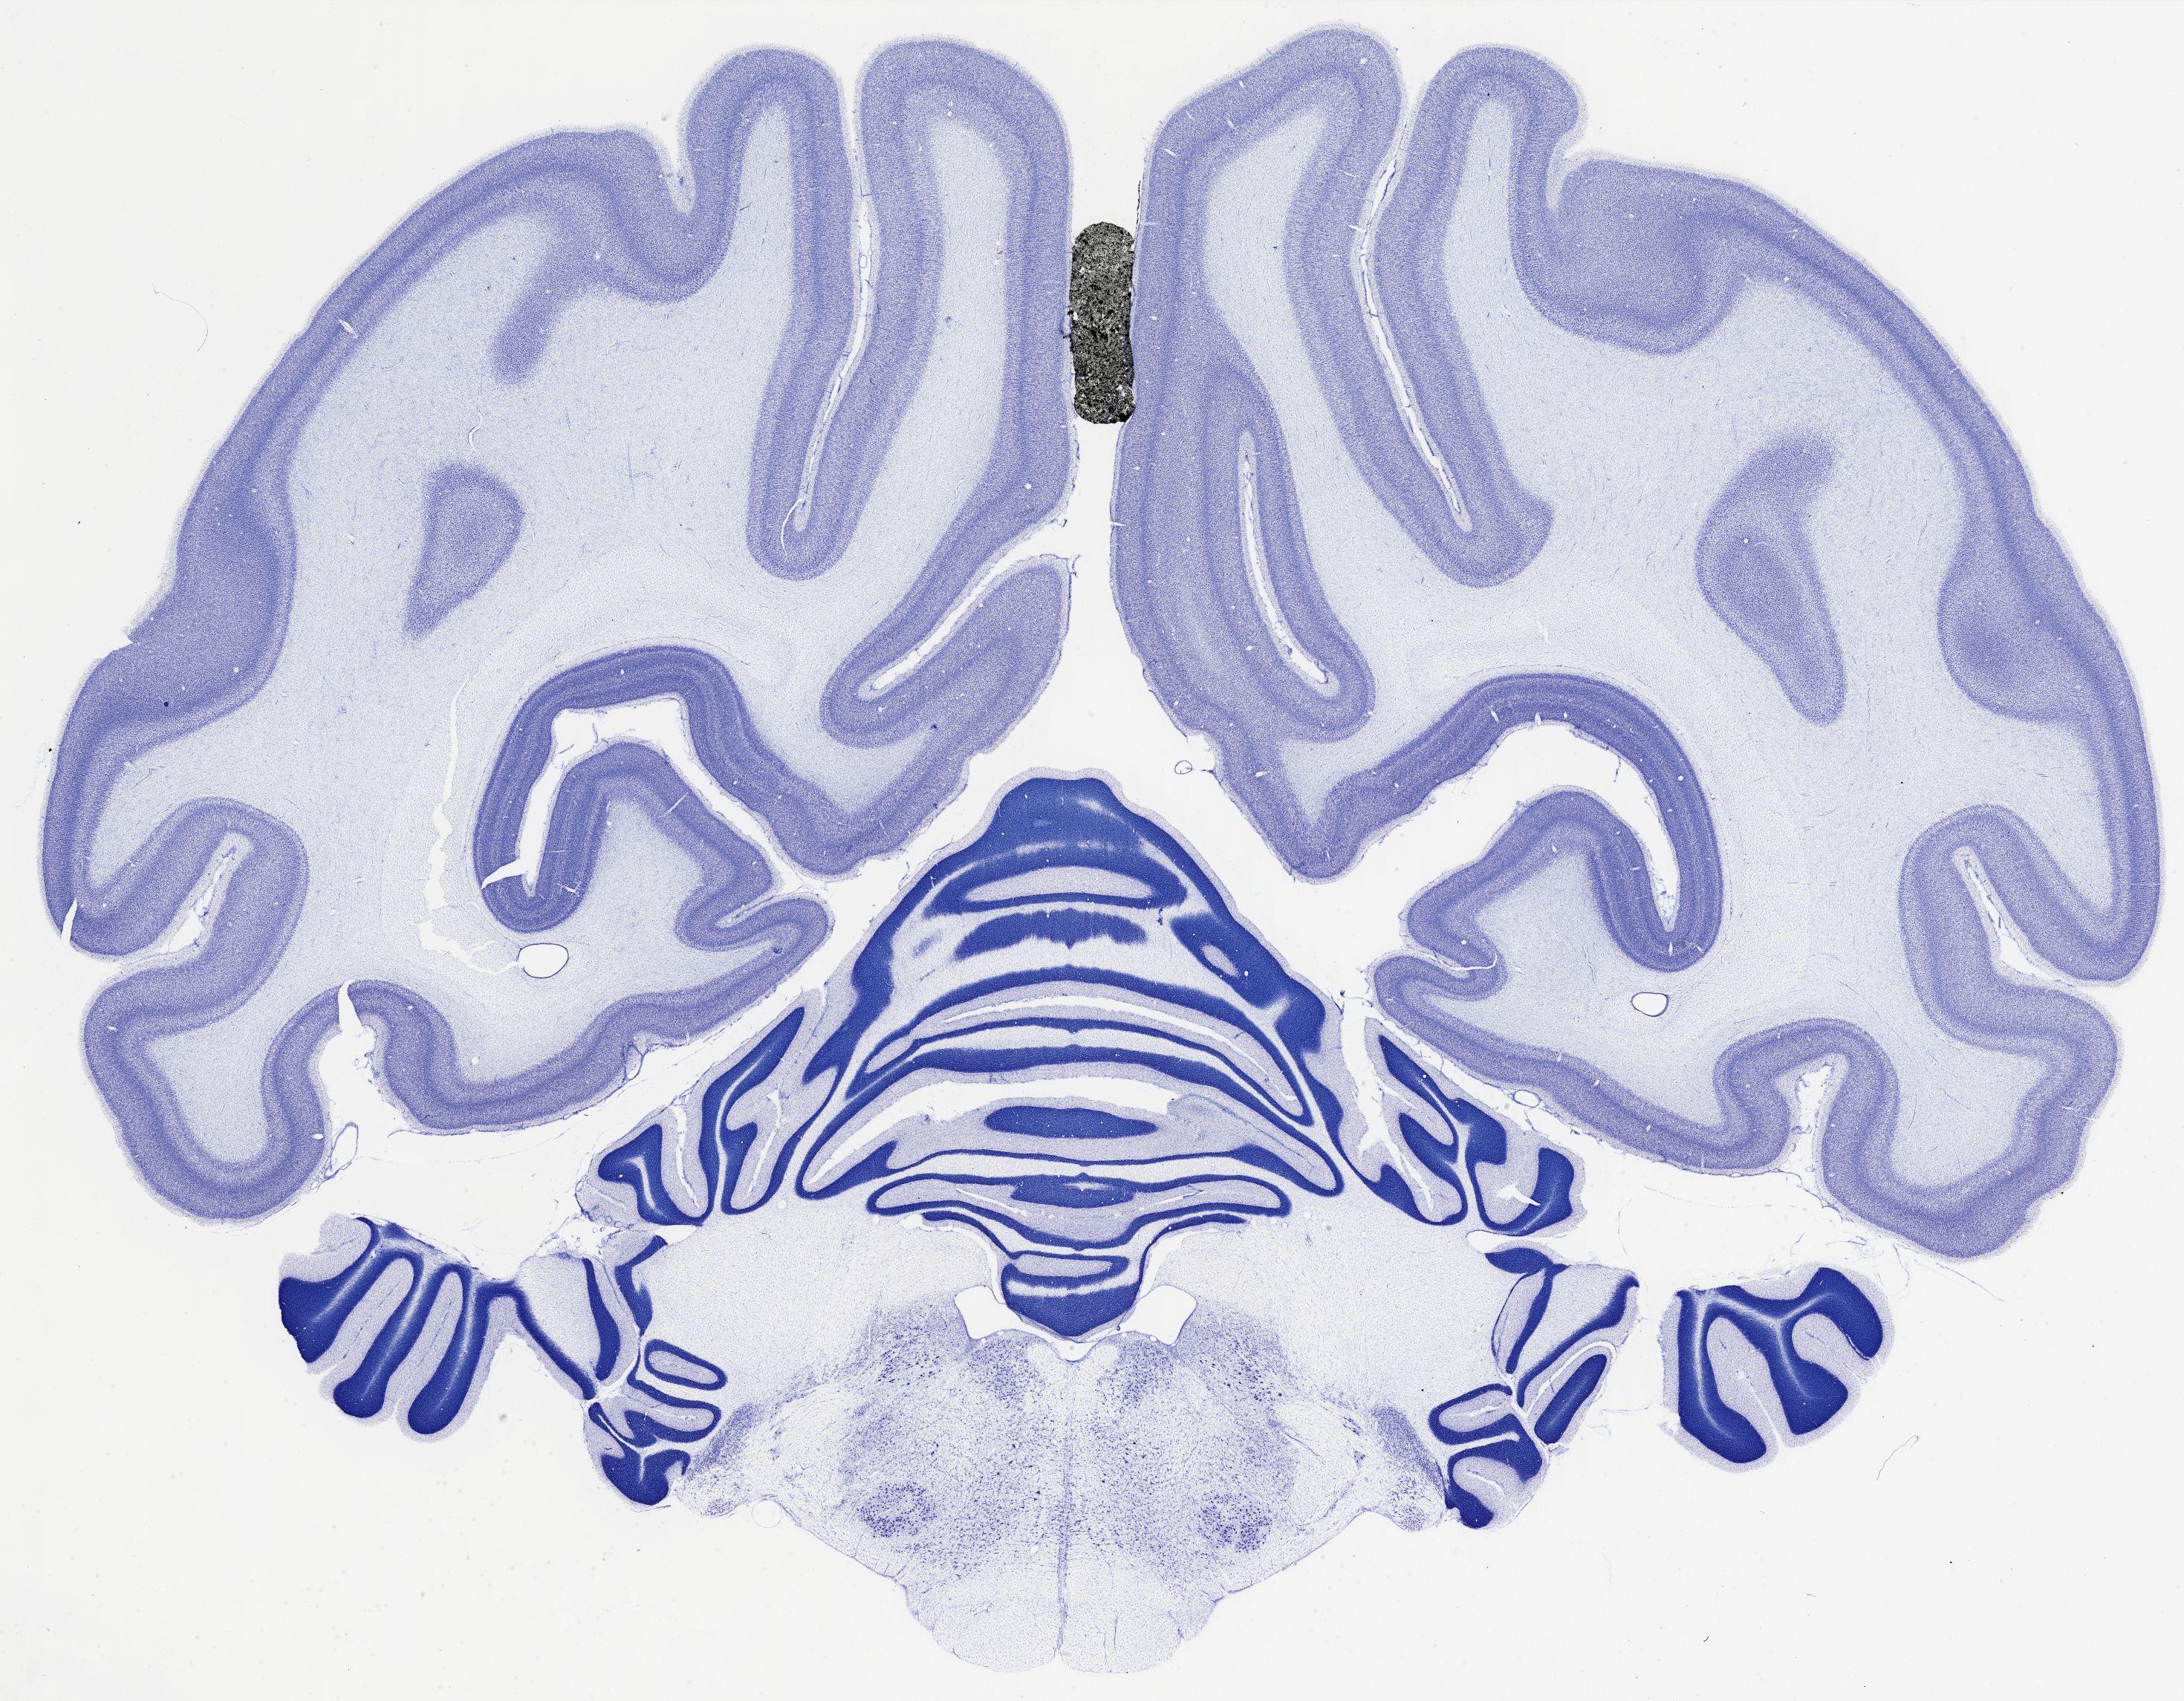

Datasets -> Chlorocebus Aethiops -> Nissl, coronal, histo, Whole-Brain, adult

[ Metadata ]   ·   Source: NeuroScience Associates

thumbnail

524